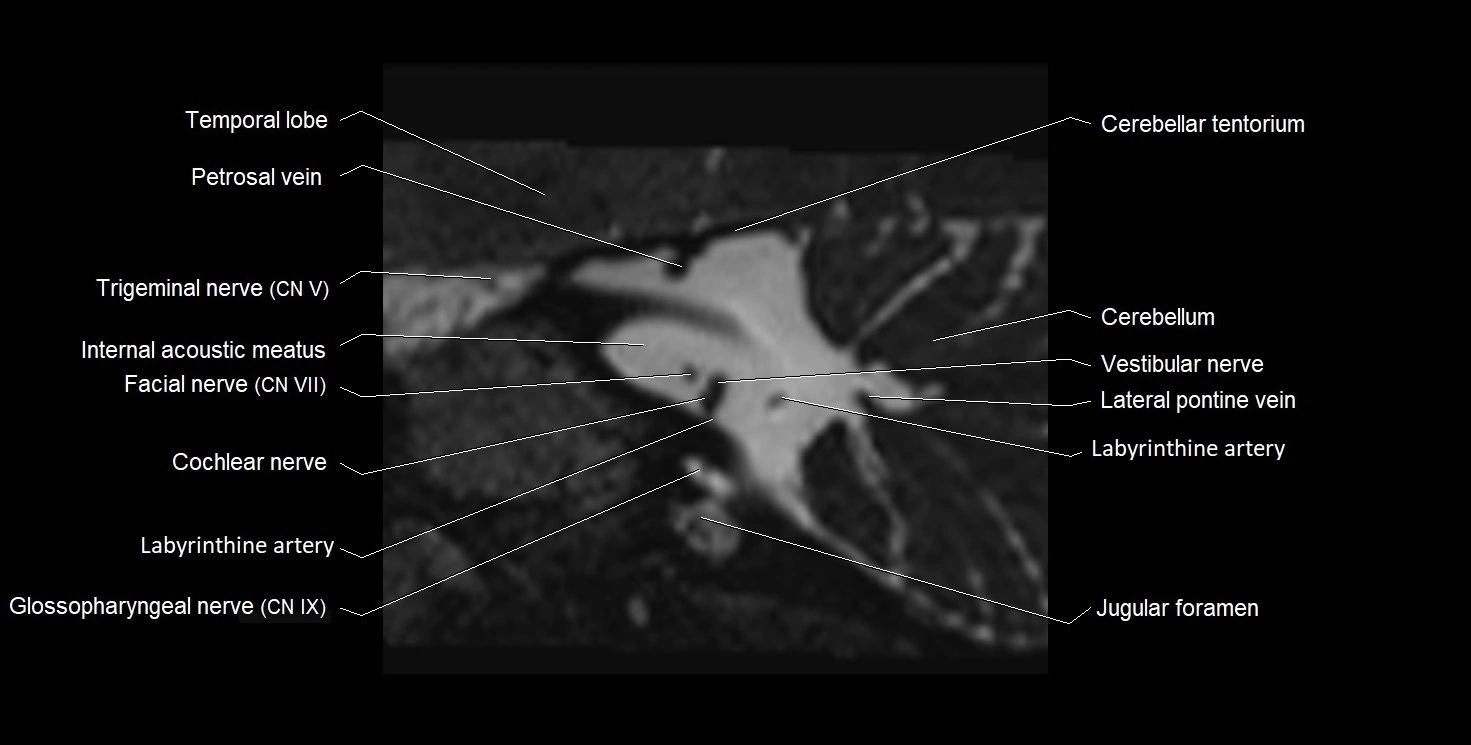

MRI images

image